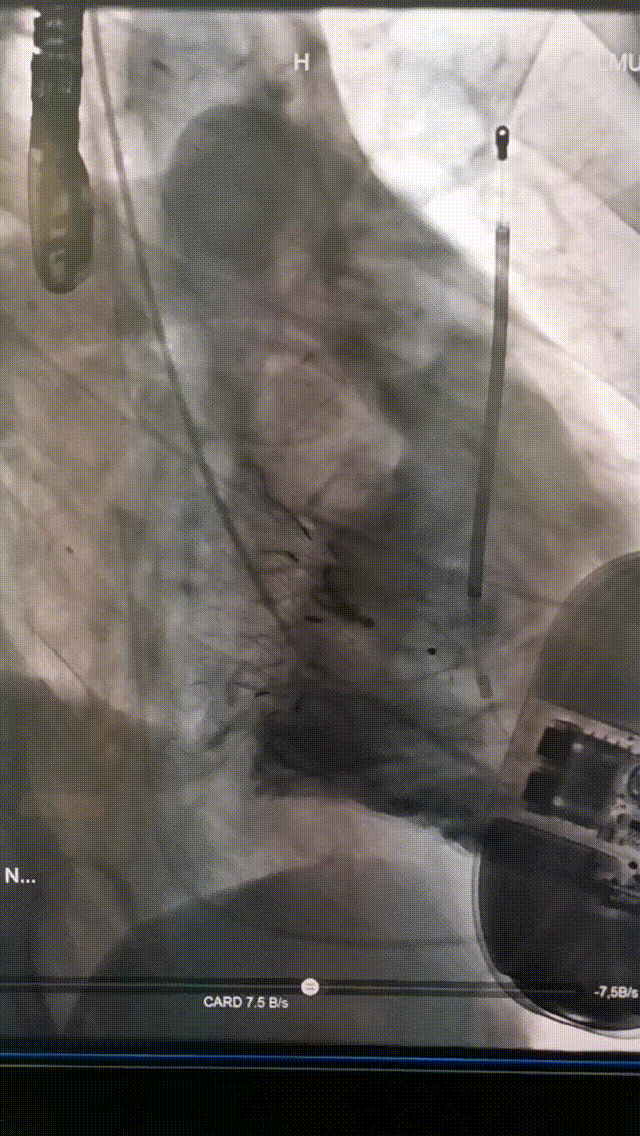

手術(shù)在全麻狀態(tài)下進(jìn)行。在加拿大圣保羅醫(yī)院的Anson Cheung教授的指導(dǎo)參與下,術(shù)者采用經(jīng)右側(cè)頸靜脈入路的方式將輸送器送入患者心臟內(nèi),在TEE及DSA引導(dǎo)下調(diào)整輸送器頭端角度,使得輸送器與三尖瓣瓣環(huán)平面垂直。在輸送器進(jìn)入右心室后釋放室間隔錨定裝置,而后釋放瓣葉夾持件(2個(gè)耳片結(jié)構(gòu))成垂直狀態(tài)。在TEE及DSA確定夾持件固定至三尖瓣葉根部且位于右室側(cè)后釋放人工瓣心房側(cè)盤片。隨后調(diào)整瓣膜同軸性以及室間隔錨定件位置(貼合室間隔),前推藏針管并固定,進(jìn)而釋放室間隔錨定裝置,并再次確認(rèn)瓣膜位置、穩(wěn)定性及同軸性,合攏輸送鞘后撤出輸送器,完成LuX-Valve Plus人工三尖瓣瓣膜的植入。